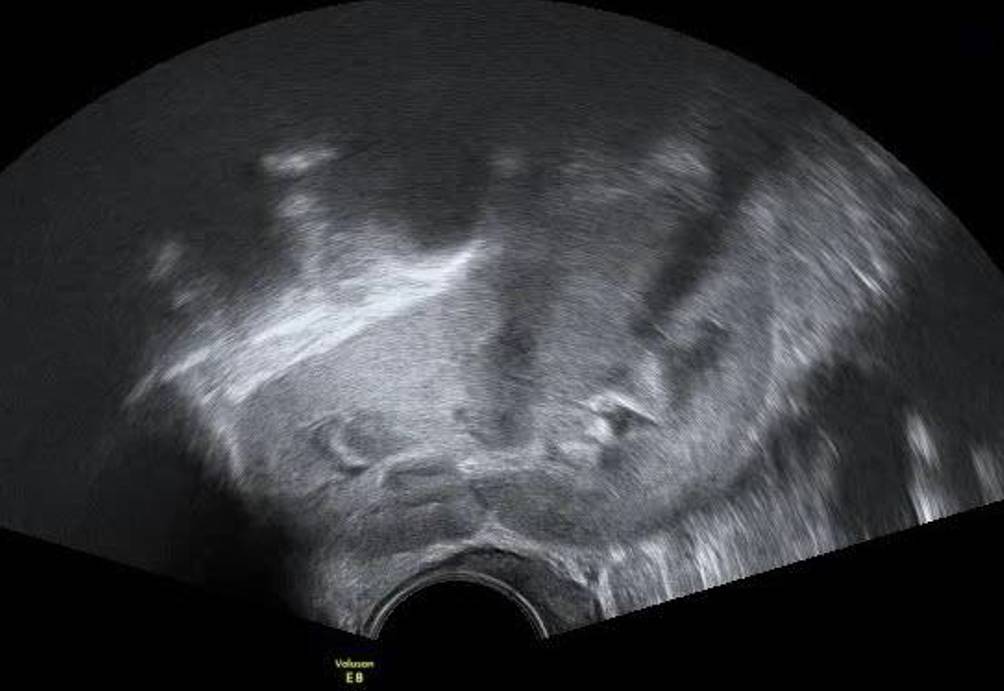

Abb. 3

Beckenniere im Vaginalschall mit zentralem Nierenbecken und Nierenkelchen

Beckennieren sind bei Frauen wesentlich häufiger als bei Männern und häufiger auf der linken als auf der rechten Seite. Meist sind sie den Patientinnen bekannt, sie können aber durchaus auch bei einem Vaginalultraschall erstmals auffallen. Es gibt auch Patientinnen, die abwarten, ob die junge Ärztin oder der Arzt ihre Beckenniere erkennt und etwas dazu sagt. Auch wer routinemäßig Nierenschälle macht, wird eine Beckenniere nicht auf den ersten Blick als solche erkennen: Da im Zuge der embryonalen Entwicklung einer Nierendystopie die Rotation der Nieren selbst gestört ist, liegt das Nierenbecken ventral des Nierenparenchyms und nicht medial (Abb. 3). Die Beckenniere sieht also nicht aus wie eine „typische“ Niere im Ultraschall und kann auf den ersten Blick auch für einen soliden Ovarialtumor gehalten werden (Abb. 4). Steht die Diagnose fest, sollte die Gelegenheit genutzt werden, gleich mit 3‑D-Ultraschall nach einer Uterusfehlbildung zu fahnden, da diese bei Nierendystopien gehäuft auftreten [8].